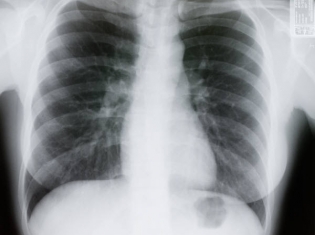

Hypophosphatasia is a rare metabolic bone disease that can lead to rickets. Bones do not harden and grow properly and this affects how the ribcage is developed causing impaired lung function.

For the study, safety, motor skills, cognitive development and lung function were all evaluated to determine if the enzyme-replacement treatment could be effective in treating hypophosphatasia. Researchers used the curing of rickets as a sign that the treatment was effective.